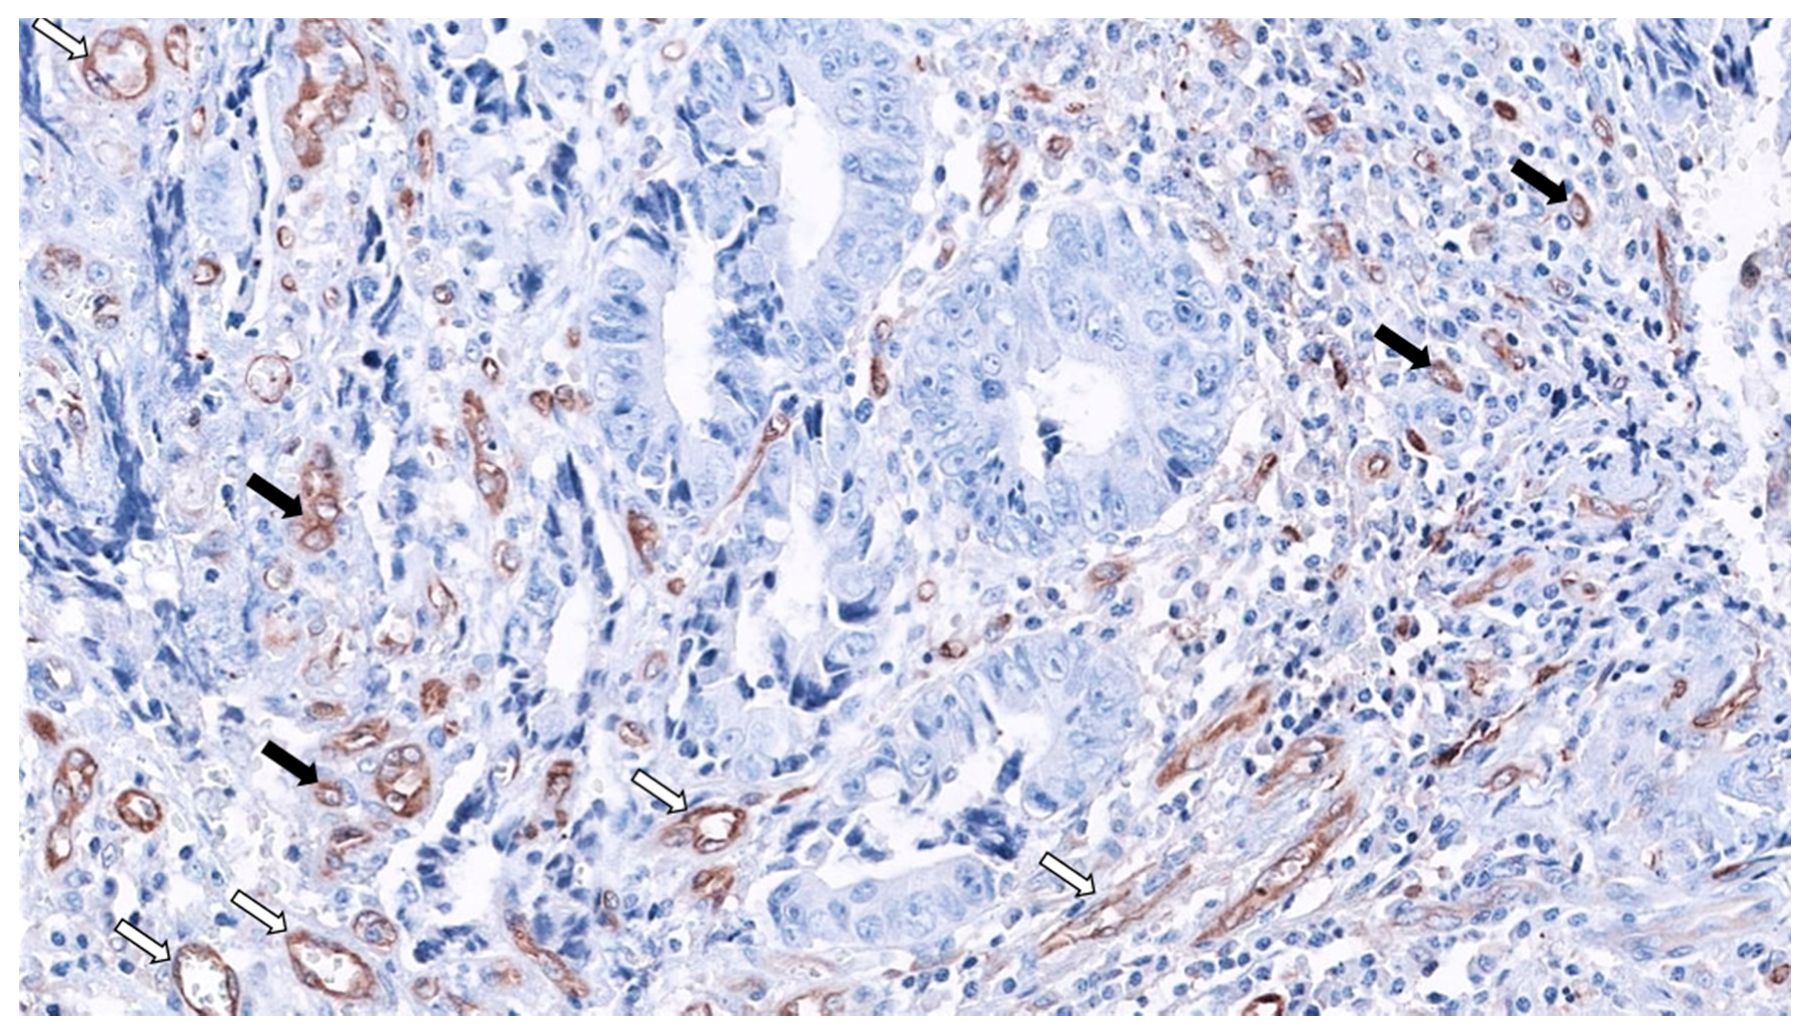

2. SAC Shows an Upregulation of Angiogenesis Markers

4. SAC Displays an Active Invasive Front